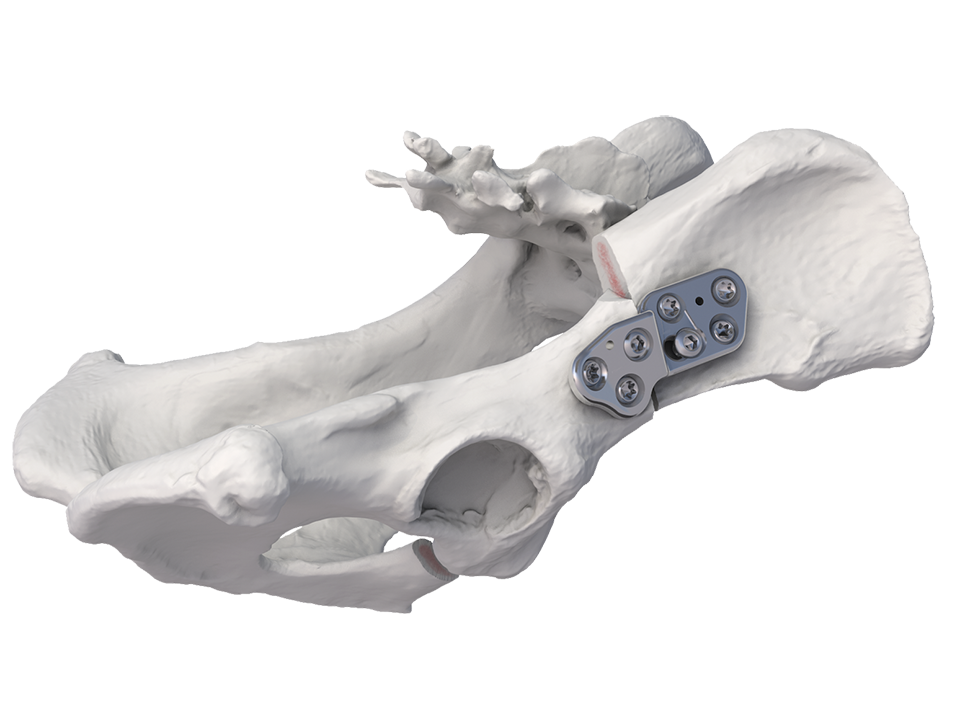

The DePuy Synthes Vet double/triple pelvic osteotomy (DPO/TPO) plate is indicated for treating coxofemoral joint instability and subluxation in immature dogs prior to the onset of osteoarthritis. The DPO/TPO plate is 3.2 mm thick and available in right and left versions with angulations of 20°, 25° and 30° between the plate surfaces so as to perform the rotational osteotomy of the acetabular bone segment.

The recently launched DPO/TPO plate offers substantial improvements to existing bone fixation plates to overcome these complications (Fig 2). Features of the plate include:

- Screw trajectories designed to optimize screw purchase into the relatively soft bone.

- Anatomically contoured to match the ilial shaft and to allow clearance for acetabular flare and the tuberosity at the origin of the rectus femoris muscle.

- Plate design includes two distinct screw-hole technologies accommodate all plating modalities (stacked combi holes and coaxial combi-hole).

- Incorporation of locking technology permits a fixed-angle device to increase construct strength.